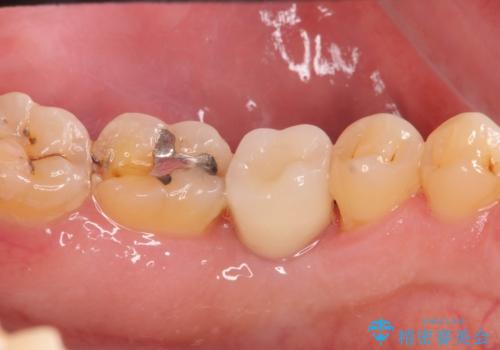

奥歯の欠損 インプラント治療

- 奥歯を失ったのち放置してしまった部位にインプラント治療を希望されて来院されました。

少量の骨造成を併用したインプラント治療を計画します。

自然な仕上がりと、久しぶりのしっかりと噛める感覚に大変満足いただくことができました。